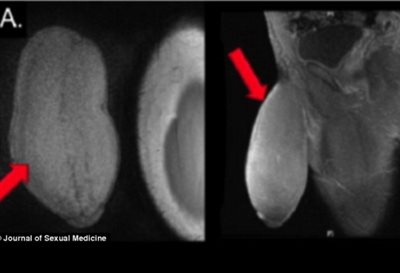

Σε επέμβαση συρρίκνωσης πέους υπεβλήθη ένας Αμερικανός 17χρονος έφηβος επειδή το γεννητικό του όργανο ήταν υπερβολικά μεγάλο και τον εμπόδιζε να κάνει σεξ και να συμμετέχει σε ορισμένα αθλήματα.

Το πέος του έφηβου είχε διάμετρο 25 εκατοστά και μήκος 17 εκατοστά. Οι χειρουργοί του περιγράφουν το σχήμα του σαν μια μπάλα αμερικανικού fotball.